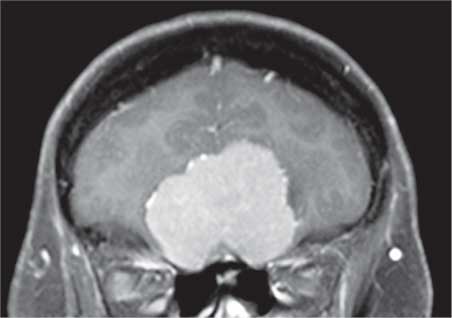

И это на самом деле так. Все повреждения передней части черепа могут нарушить их функционирование. На рисунке 36 можно видеть, как большая менингиома, доброкачественная опухоль, растущая из ткани, окружающей мозг, захватывает его именно в том месте, где обонятельные нервы проникают в череп. Естественно, что аносмия является обычным симптомом при заболеваниях подобного рода.

Рис. 36. Большая светло-серая масса, расположенная над носовыми полостями, это менингиома; в результате ее разрастания нарушается функционирование обонятельных нервов в том месте, где они проникают в череп